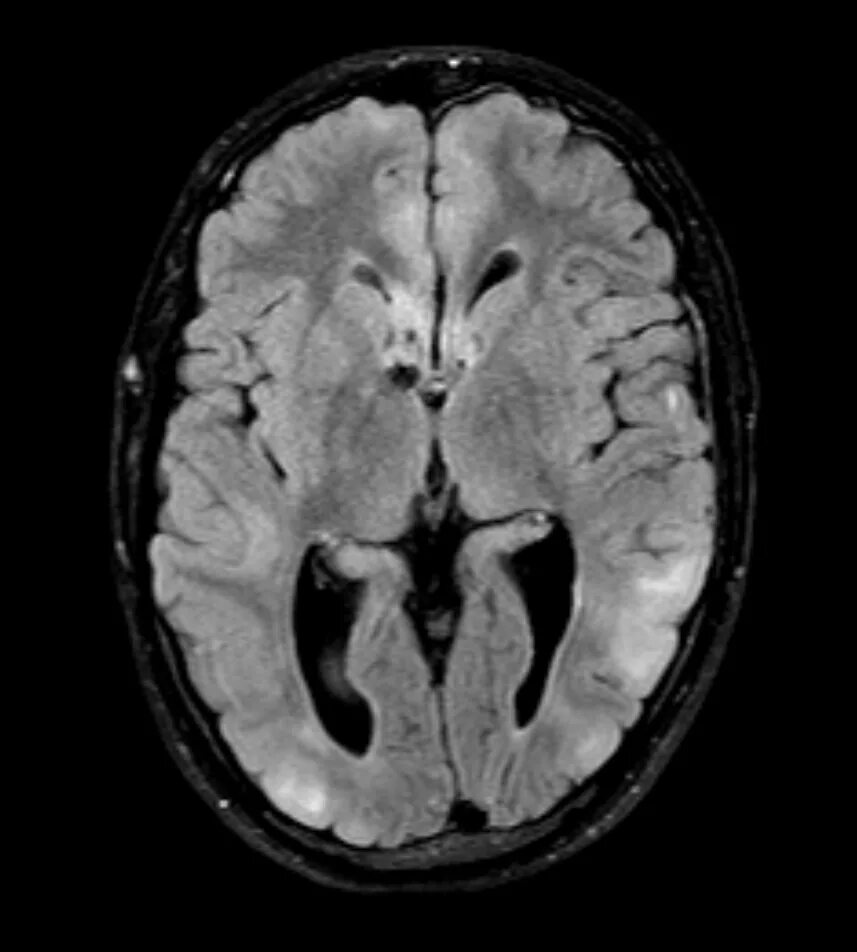

Туберкулезный склероз